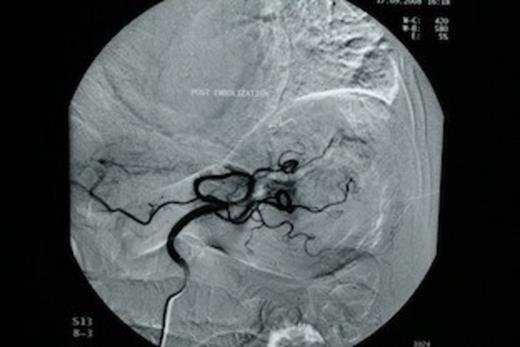

The patient was subjected to emergency oesophago-gastroduodenoscopy, which revealed extensive angiodysplasia of the gastric body. At first, conservative management was attempted with intravenous fluids and transfusions. After initial stabilization of the patient (Ht: 32.5%, 90bpm, 110/50mmHg), rebleeding was encountered within 48 hours and therefore decision for interventional radiology, embolization of the angiodysplasia, was made. Urgent angiography of the left gastric artery revealed extravasation of contrast material from the gastric body (Figure 1). Following that, successful arterial coil embolization, using super selective catheterization was achieved in the distal and proximal parts of the ruptured vessel (Figure 2). Consequently the patient recovered from the hemorrhagic shock.

Urgent angiography of the left gastric artery revealed extravasation of contrast material from the gastric body